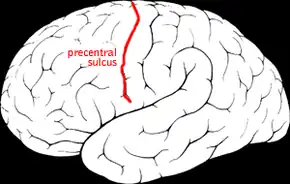

Precentral sulcus of the human brain. | |

Position of precentral sulcus (shown in red).